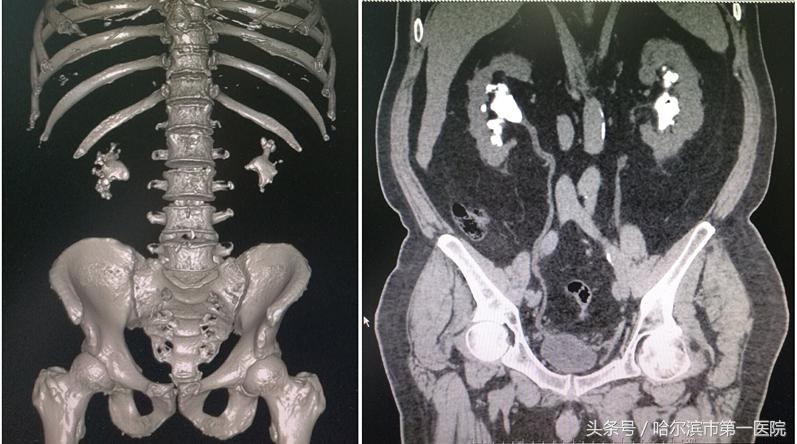

铸型结石术前三维CT影像

检查中发现,曹先生的结石最大径线45×36mm,像一个“鹿角”一样,已经塞满了左侧肾盂和各个肾盏。经过术前讨论后,具有多年微创碎石取石经验的哈尔滨市第一医院泌尿外科专家孙长华主任采取了“经皮肾镜超声碎石取石”的治疗方案。术中通过用超声在左侧后腰精准定位,然后打一个直径约0.8公分的通道,用超声弹道碎石系统击碎结石,并将碎石吸出体外,仅用半个小时,就彻底清除巨大结石。术后复查,无结石残留,6天后病人痊愈出院。

据孙长华主任介绍,铸型结石也称鹿角形结石(有时也称为珊瑚形结石),是肾脏内的一种特殊形状的结石,因其形状似鹿角而得名,也因为它像水泥浇铸一样填充于肾脏的集合系统而称铸型结石。通常是小结石不及时治疗或反复感染的结果。这样的结石插入盏口内分散较大,像“生姜”样不规整,根据肾盂形态生长,各个盏口内均有结石,因此在治疗时难度很大。